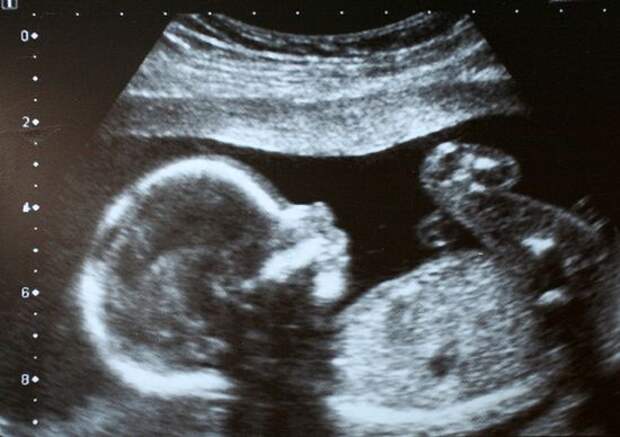

…На следующий день после венчания молодая пара поехала в дорогую частную клинику, где счастливая новобрачная сделала аборт. Когда друг-священник узнал об этом, плакал как ребенок.

Каждый год в нашей стране совершается более трех миллионов абортов. И большинство этих детоубийц, счастливых, успешных, молодых и не очень, по всей видимости, крещены в православную веру. Они встают с утра и идут убивать своих детей. Каждый год три миллиона изрезанных скальпелями, вытравленных кислотой невинных и непрощённых. Один Екатеринбург и половина Калуги под нож. А потом мы говорим про любовь. И тогда Ангелы затыкают уши и начинают плакать. Вдумайтесь, как звучит: «Я беременна, но это временно, и будет так, как мы захотим». «Мы оставили отпечатки наших ботинок на Луне, и когда возвращались, Бога там не встречали». Это утвердило нас в собственном превосходстве и стало началом нашего конца. Нет ни одного зверя, у которого не было хотя бы капли жалости. Но у нас нет жалости. Потому что мы не звери…